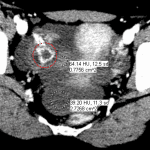

- Peripherally-enhancing structure in the right ovary with crenulated margins

- Moderate volume hemoperitoneum layering in the anatomic pelvis

- Ruptured ovarian cyst

Moderate hemoperitoneum likely from a ruptured ovarian cyst. Higher density blood clot adjacent to a right ovarian corpus luteal cyst favors this as the causative lesion.